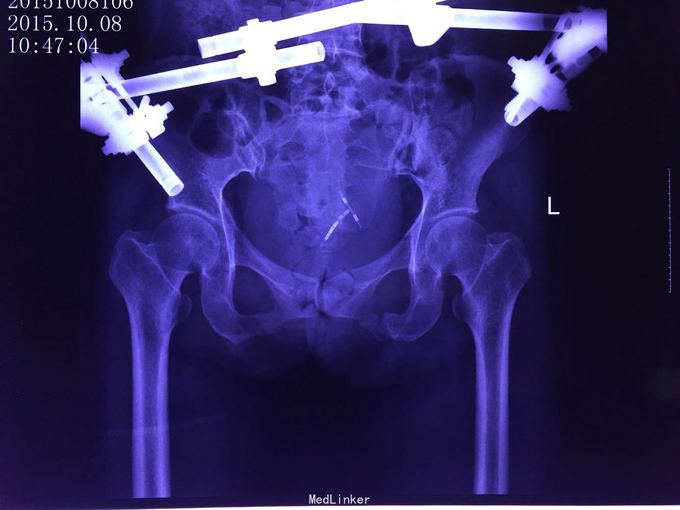

外伤后腰部疼痛伴双下肢感觉运动障碍2月余。 患者马某,女,41岁,2015年8月26日从三楼摔下,当时即出现腰部及下肢的感觉运动障碍,拍片诊断为"1,腰1骨折脱位并神经损伤。2,骨盆骨折,3,双侧肺搓伤并胸腔积液。"并及时对症行手术治疗。

病情稳定后转入我康复医院,现骨盆外固定架已去除,感觉平面右侧自膝关节以下开始减弱,左侧自左踝处开始减弱,二便功能障碍,右下肢髋关节肌群肌力2级,股四头肌,胫前肌等肌力3级,左下肢诸肌群肌力3级。